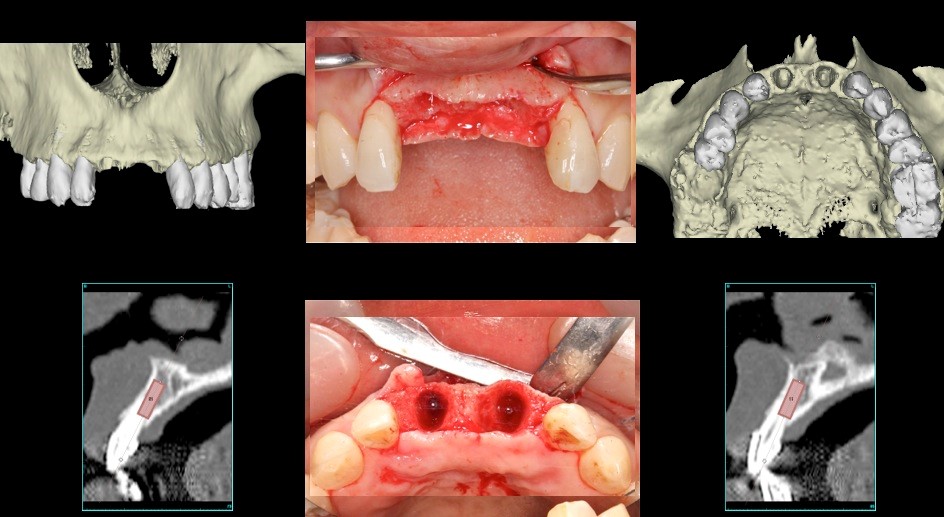

上顎中切歯 抜歯即時のケース

上顎前歯部フライスドリルで形成(直径3.5㎜)埋入インプラントは10㎜の計画であるがフライスドリルでは14㎜まで骨採取のために形成する 深度ゲージで深度確認 形成部位に骨尖を確認することができる(左上1)(右上1はすでに骨採取後)